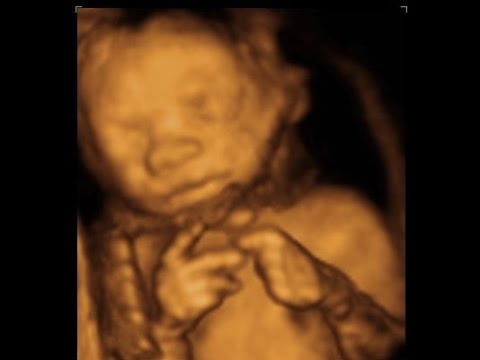

19. Haftada fetus (bebeğin 3. Aydan doğum sürecine kadar olan evresinin adı) dış dünyadan gelen sesleri algılamaya başlar. Yani bebeğiniz anne rahmindeyken sizin seslerinizi yavaş yavaş seçmeye başlar. Kas ve sinir sistemi de şekil almaya başladığından elleri ve ayaklarını hareket ettirebilir. Yaptığı bu hareketler büyük çapta olmadığından hissetmeyebilirsiniz. Fetusun cildinde de değişmeler yaşanır. Çok uzun bir zaman diliminde sıvı dolu bir ortamda büyüyen fetusun cildinin bu ortamdan etkilenmemesi için vücudunun dış yüzeyi kremsi bir madde ile kaplanır. Bu maddenin ismi vernix caseosa’dır. Bebek bu haftada rüya uykusunda rüya görmeye başlar. Cinsiyet kız ise yumurtalıkları gelişmeye başlar.

19. Hafta fetusun gelişiminin devam ettiği bir haftadır. Bu haftadan sonra gelişim sürecek fakat gelişim hızı yavaşlayacaktır. Fetusun boyu yaklaşık 22 santimetreye kilosu ise yaklaşık 210 grama ulaşacaktır.

Fetus ellerini ve ayaklarını oynatabilir. Doğru pozisyonda duruyor ise bebeğin cinsiyeti söylenebilir. Bebeğiniz bu kadar hormonsal bir yoğunlukta gelişirken annenin de vücudunda değişimler meydana gelmektedir.